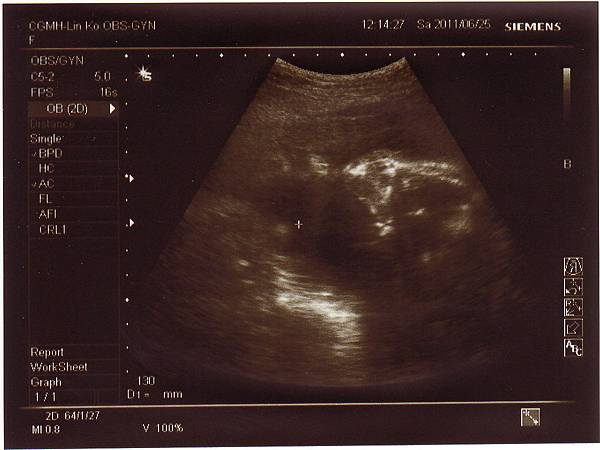

2011.06.25 當天先去超音波室做了仔細的超音波檢查,

檢查心臟.是否兔唇.手腳.肺動脈....等等,

一切都非常正常,也確定是個兔女郎!

只是後來到診間時,醫生聽寶寶心跳有幾秒是比較慢的,